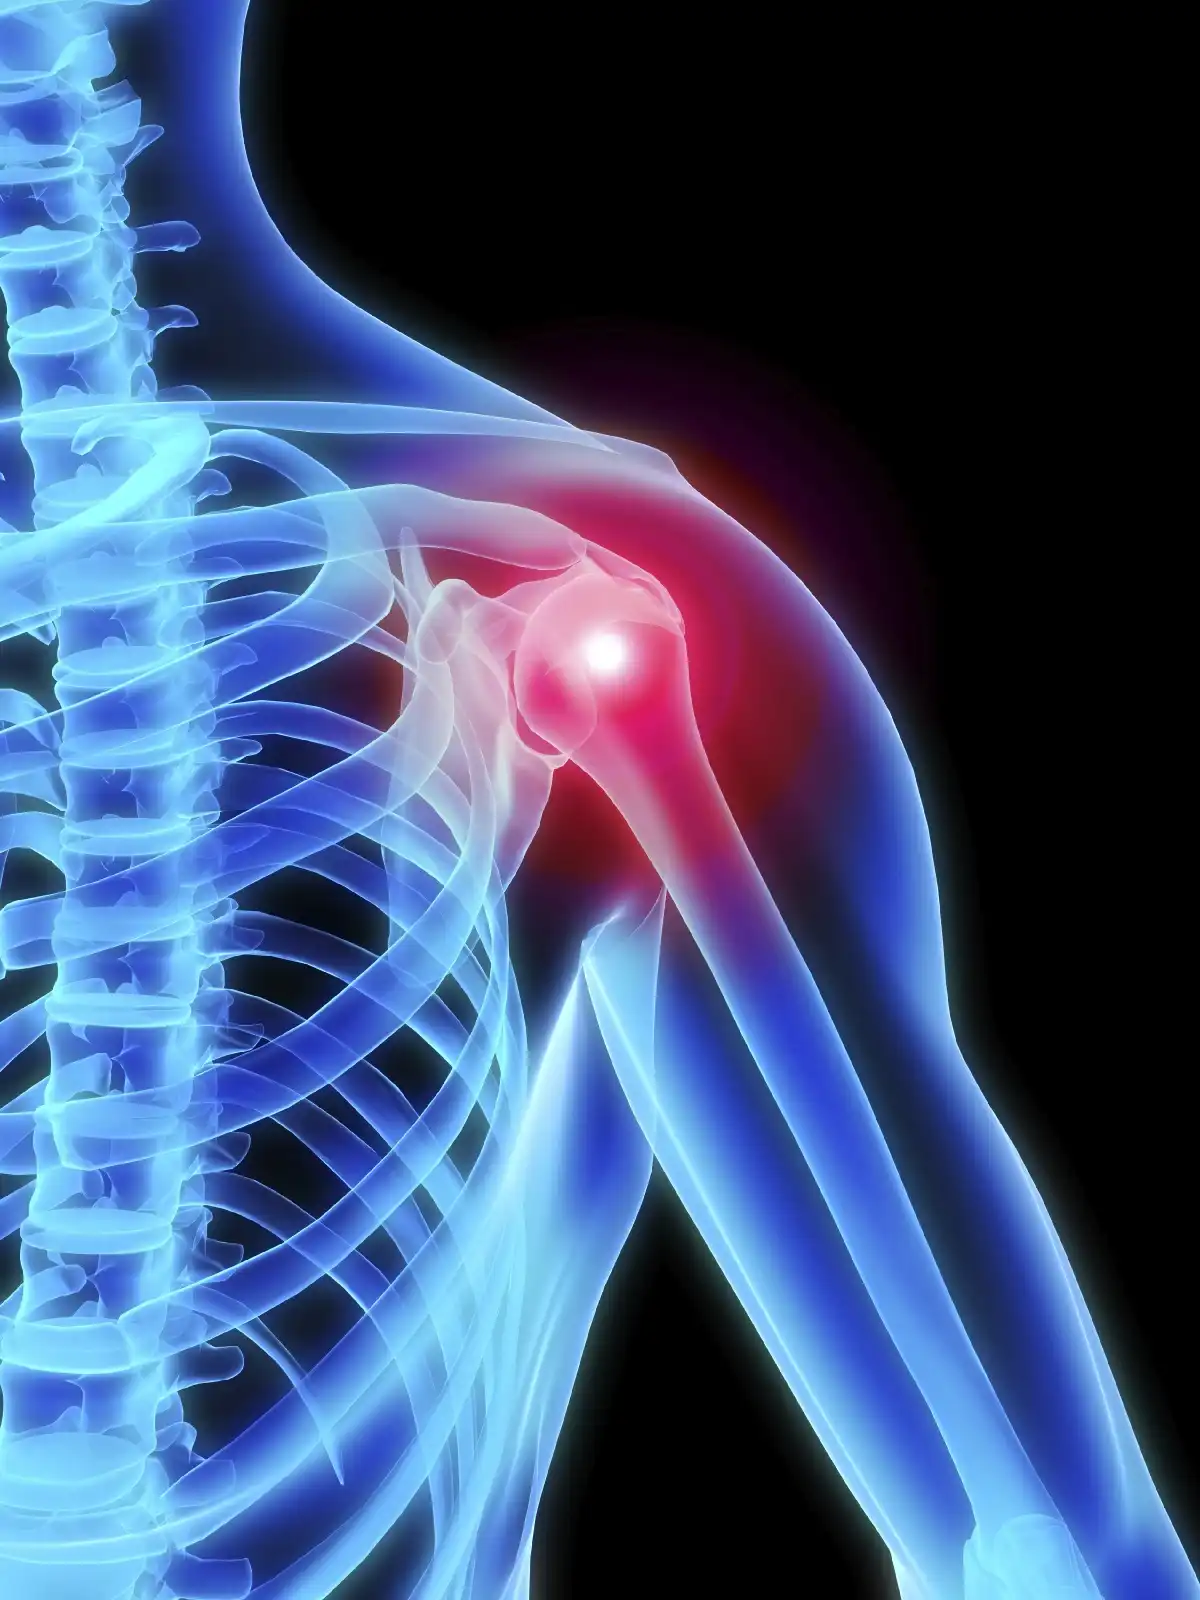

پارگی تاندون روتاتور کاف (Rotator cuff) | علائم، دلایل، روشهای درمان و فیزیوتراپی تخصصی در سال1405 ادامه مطلب »

همهچیز درباره عمل پارگی تاندون شانه در سال 1405 | مراحل جراحی، نکات طلایی و مراقبتهای بعد از عمل ادامه مطلب »

جراحی مفصل شانه در سال 1405 | قیمت، نکات طلایی و راهنمای قدمبهقدم برای بازگشت بدون درد ادامه مطلب »